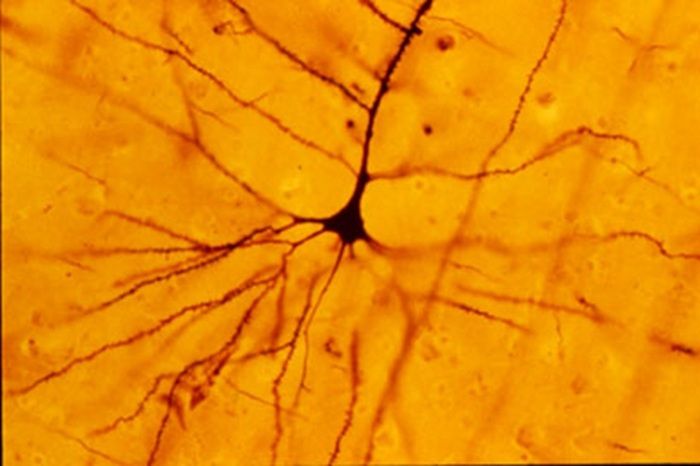

Dalla scoperta dei cosiddetti neuroni specchio , che si attivano sia quando compiamo un'azione sia quando la osserviamo fare a qualcun altro, agli studi che hanno fatto luce sulla malattia di Huntington , un raro disturbo genetico neurodegenerativo per il quale si stanno ora sperimentando possibili terapie. Tanti degli sviluppi compiuti oggi nel campo delle neuroscienze rappresentano l' eredità di Camillo Golgi e della sua ' reazione nera ': la tecnica di colorazione da lui sviluppata nel 1873 , che permise per la prima volta di evidenziare e osservare le singole cellule cerebrali .